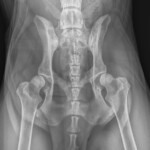

The Whyalla Veterinary Clinic has a new Shimadzu MUX10 Xray machine for high quality radiographs and a new Agfa XD14 Csi Tethered panel to produce outstanding direct digital Xrays from the images from the Shimadzu MUX10 Xray machine.

The XD14 CsI Tethered Panel is an integral part of an Agfa HealthCare’s Instant DR solution, which includes the NX image acquisition software with MUSICA3 processing and detector. These cassette-less and filmless solutions provide a range of workflow benefits that improve quality, productivity and speed up exam time.